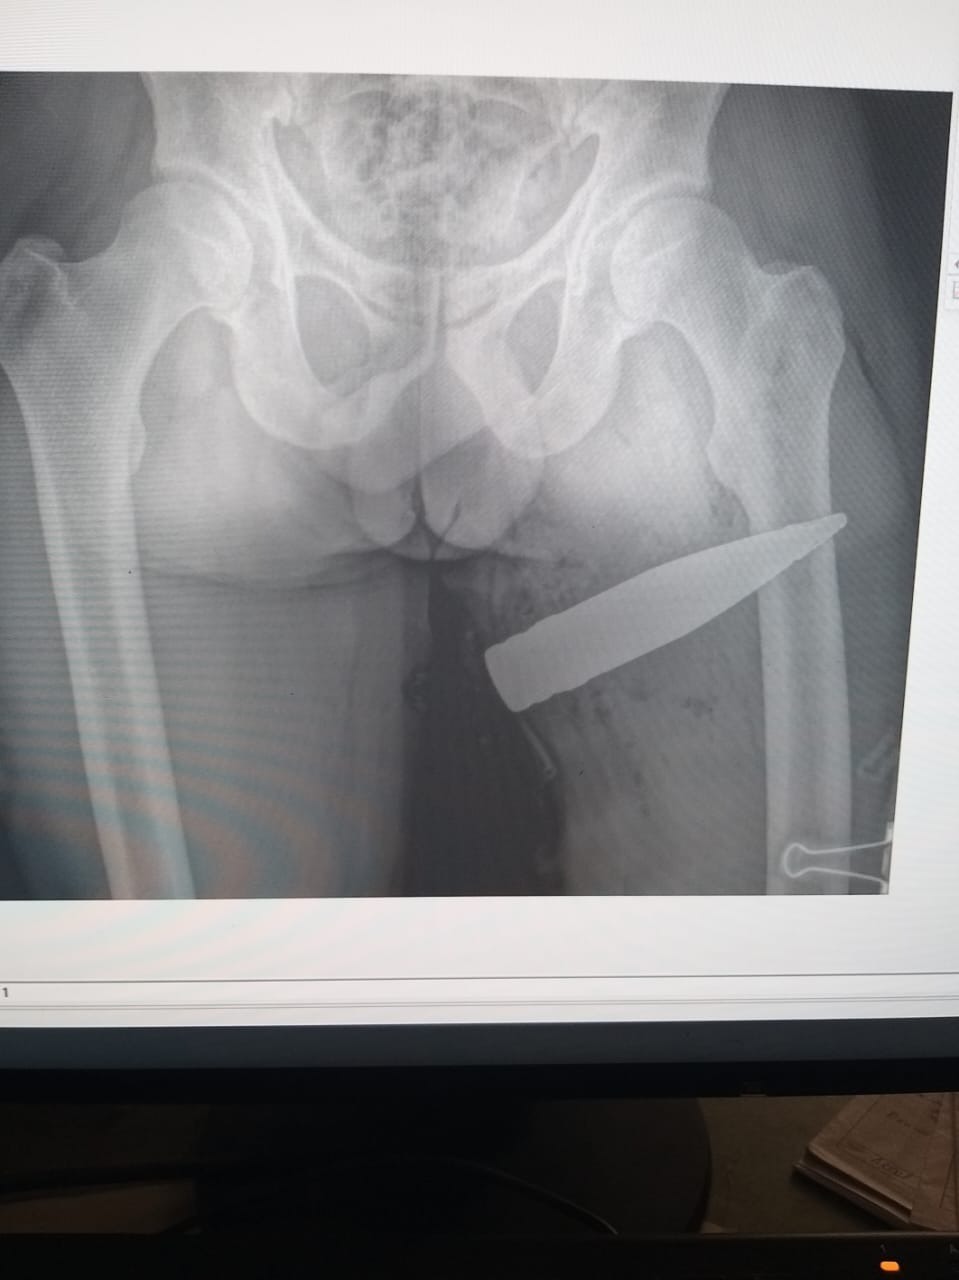

Врачи Башкирии достали снаряд из бедра бойца СВО

Именно Салават Ахметнурович был тем врачом, который принимал бойца со снарядом. У пострадавшего мужчины в бедре застрял осколок. Но когда сделали рентгенографию, стало очевидно, что ситуация еще более жуткая.